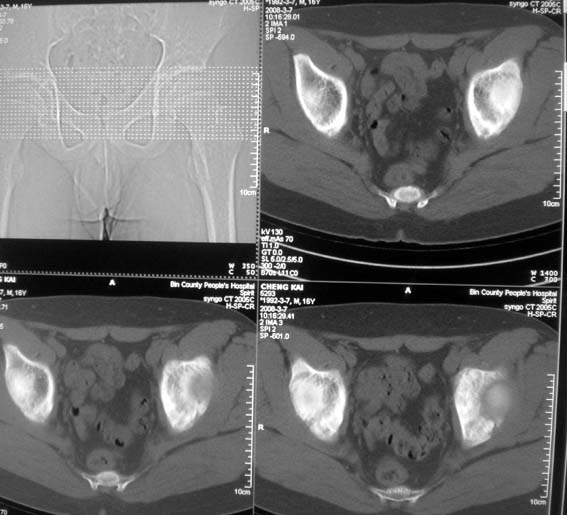

男,16岁,髋部疼痛,发育延迟。

考虑:双侧髋臼发育不良性骨病。

双侧髋臼发育不良性骨病

双侧髋臼发育不良性骨病.股骨头早期坏死?

双侧髋臼发育不良性骨病(髋臼窝变浅,髋臼内上缘关节面毛糙)。

考虑:双侧髋臼发育不良性骨病